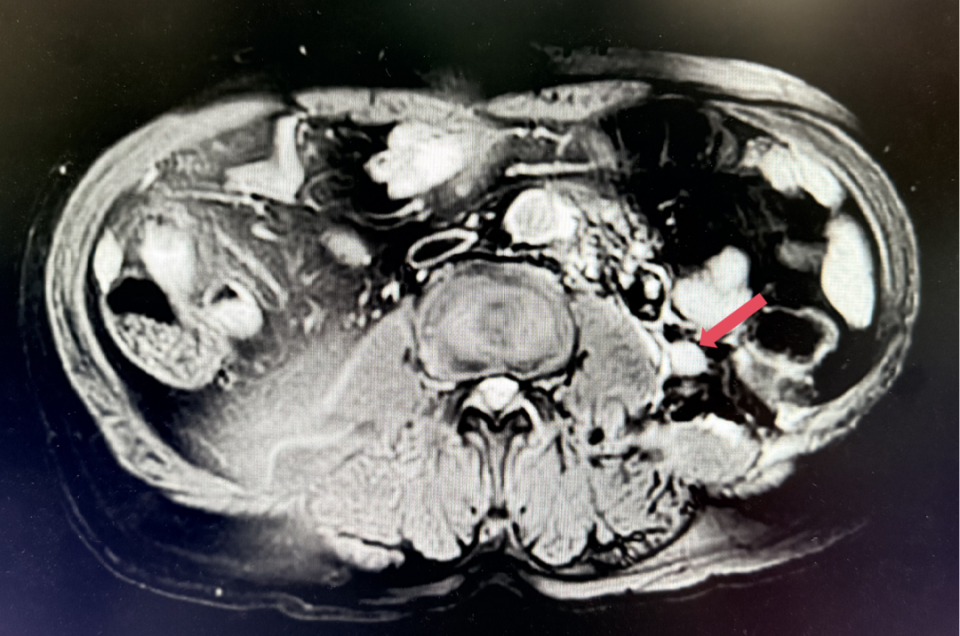

2023年11月,最深应答